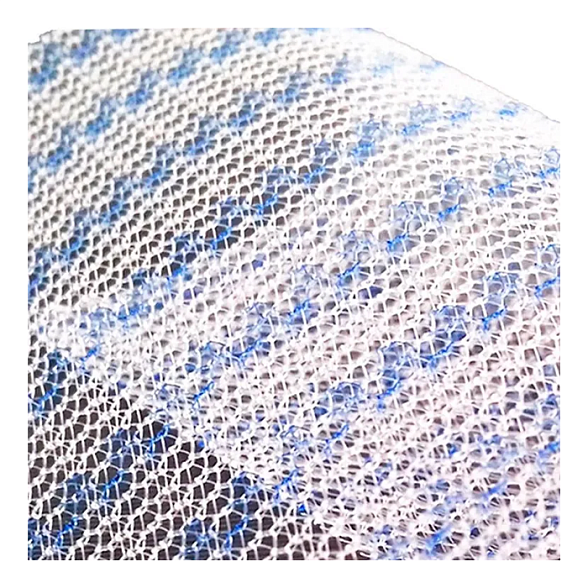

Эндопротез-сетка (сетка хирургическая) полипропиленовый для восстановительной хирургии ЭСФИЛ лёгкий, 8х12 см, Линтекс

Эндопротез-сетка полипропиленовая ЭСФИЛ лёгкий для восстановительной хирургии

Эндопротез-сетка ЭСФИЛ лёгкий от компании «Линтекс» — это современное и надежное решение для пластики грыж и восстановления целостности мягких тканей. Изделие представляет собой полипропиленовую сетку, специально разработанную для обеспечения прочной и долговечной поддержки в области хирургического вмешательства.

Ключевой особенностью данной модели является её «лёгкая» конструкция. Это означает, что сетка изготовлена из тонкого, но высокопрочного полипропиленового мононитяного материала с пониженной плотностью. Такой подход минимизирует количество имплантируемого инородного материала, что способствует лучшей интеграции с тканями организма и снижает риск послеоперационного дискомфорта для пациента.

- Оптимальная интеграция: Макропористая структура (размер пор более 1 мм) позволяет фибробластам и коллагеновым волокнам свободно прорастать через сетку, обеспечивая её надежное закрепление и естественное укрепление тканей.

| Тип плетения | Макропористая, монофиламентная сетка |

| Цвет | Белый / синий (для удобства ориентации на операционном поле) |